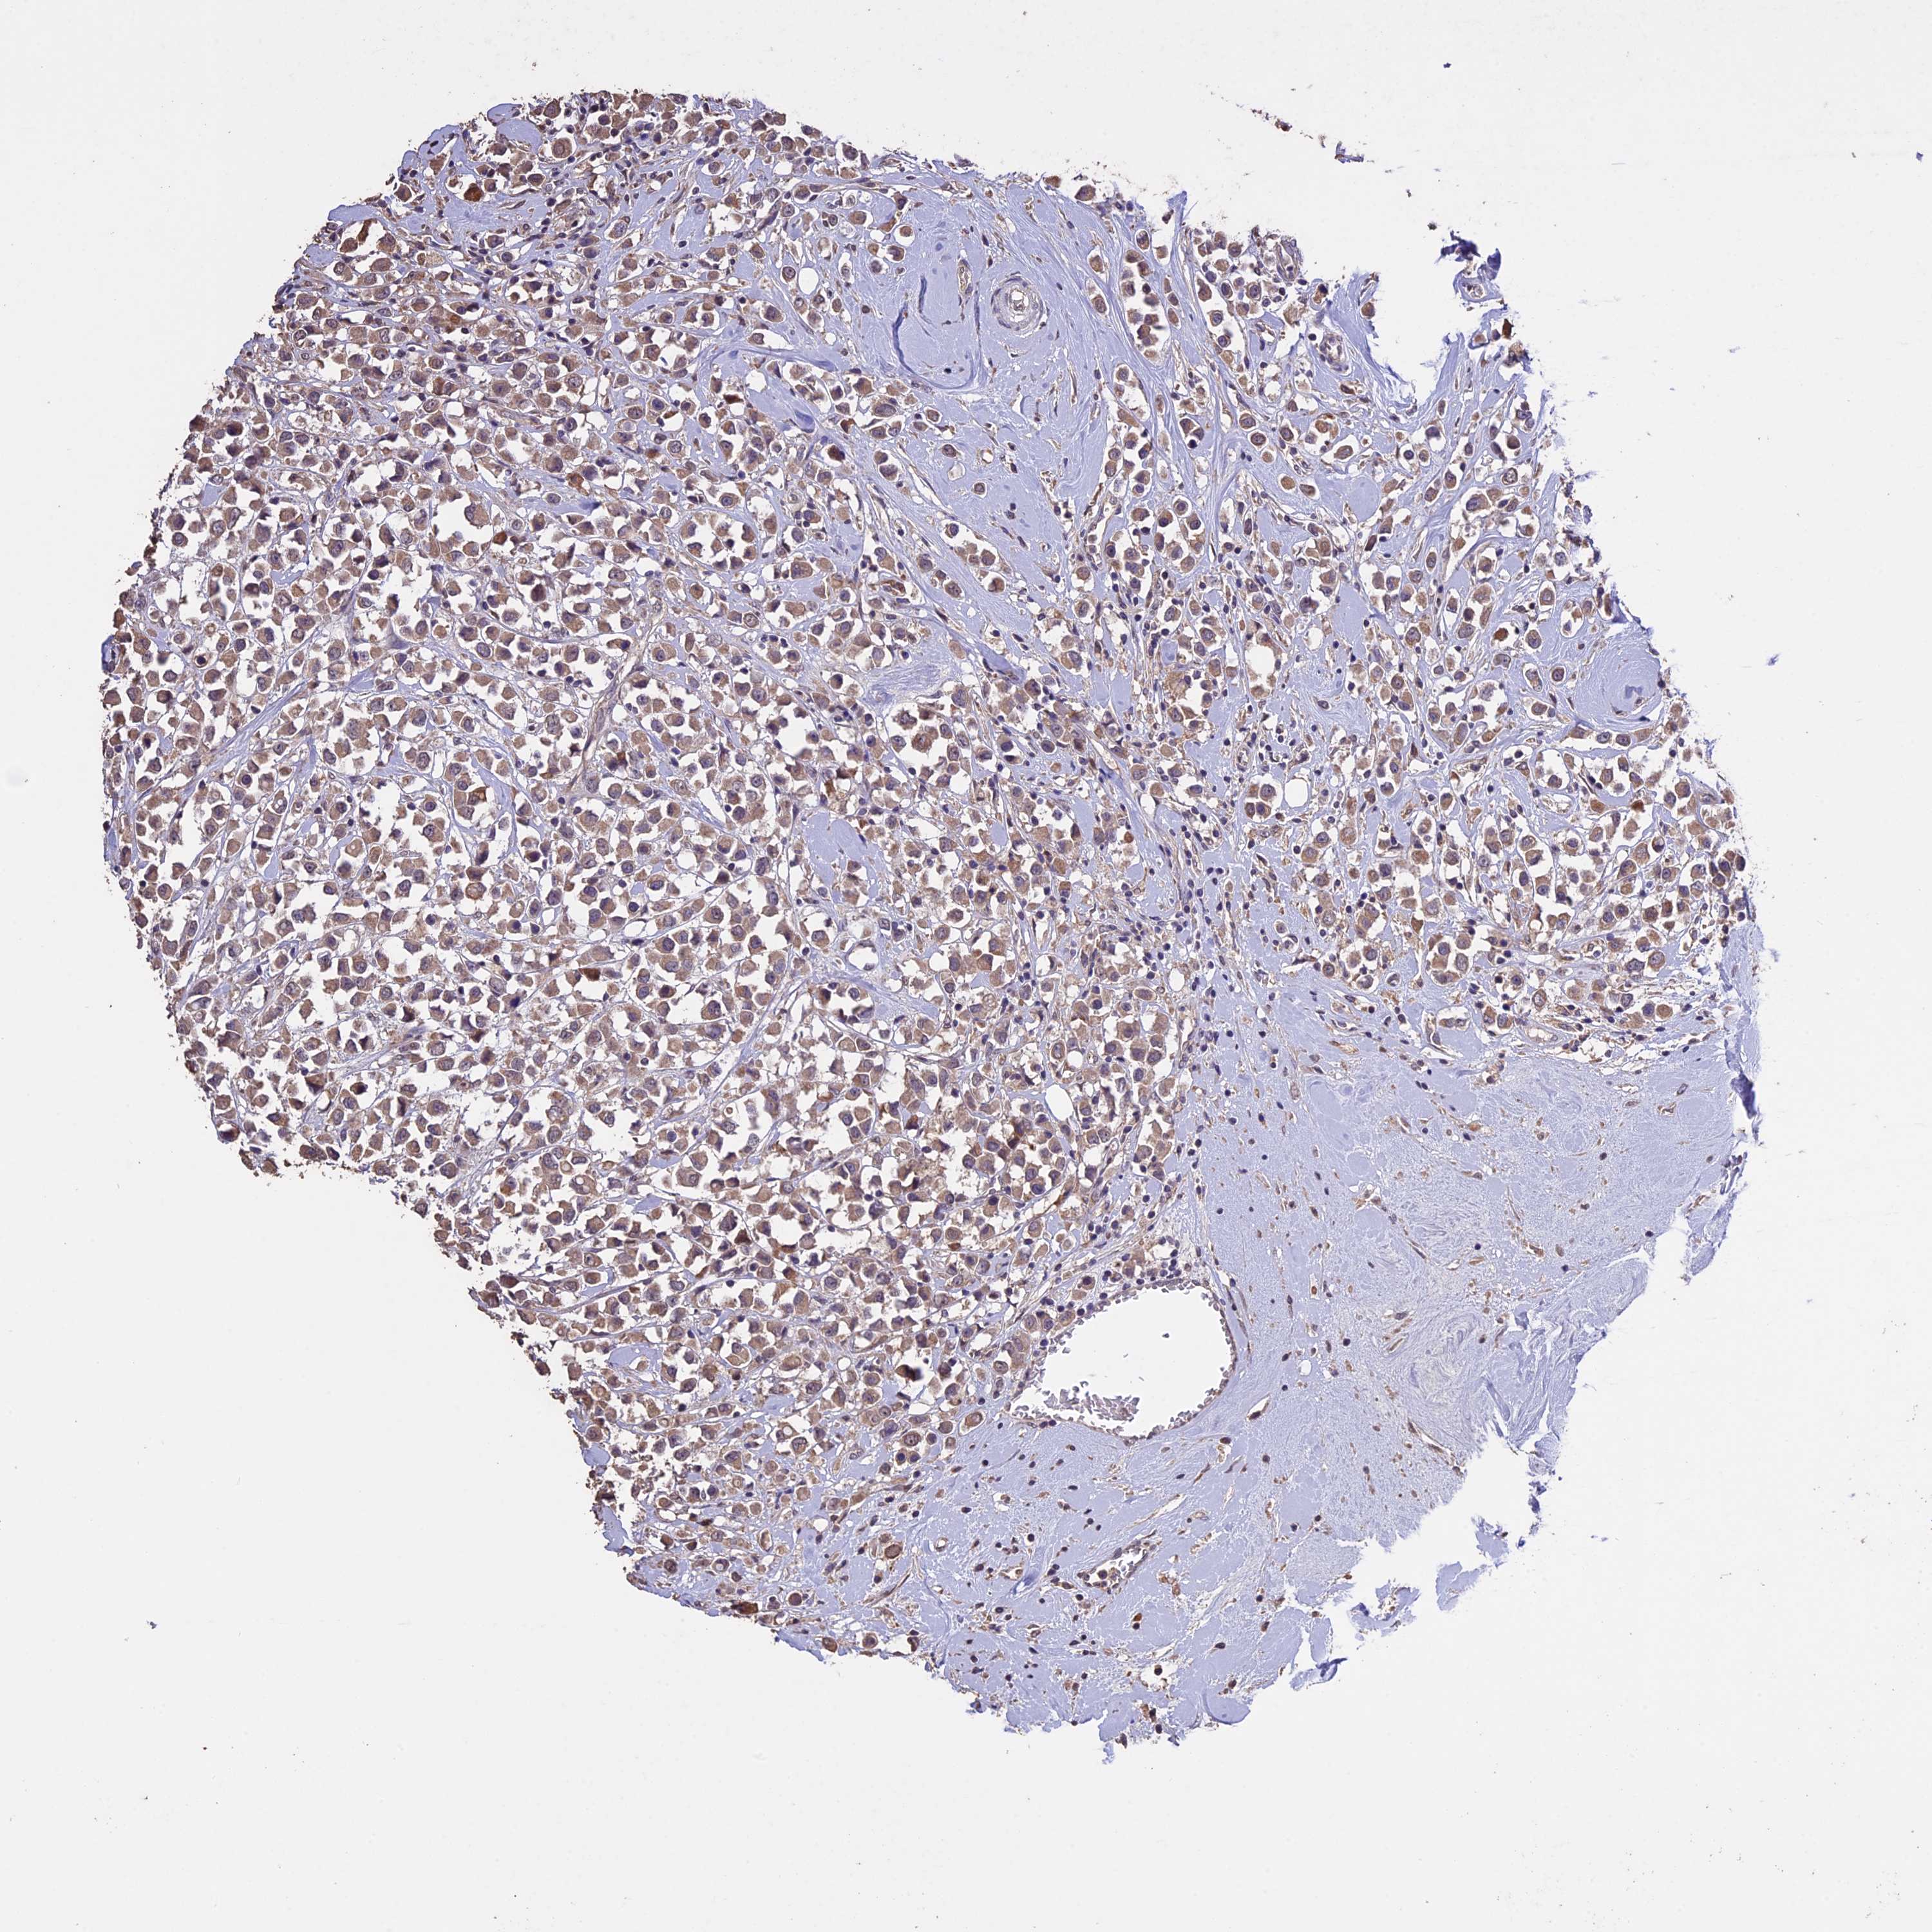

CANCER BREAST CANCER Show tissue menu

BRCA TCGA BRCA VALIDATION PROTEIN EXPRESSION

Breast cancer

Human cancer

DIS3L is not prognostic in Breast Invasive Carcinoma (TCGA)